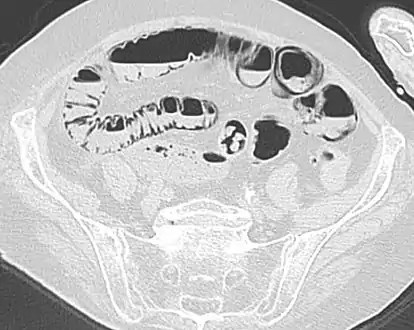

Pneumatosis intestinalis

Close-up of intestine of infant showing necrosis and pneumatosis intestinalis (autopsy)

Pneumatosis intestinalis (also called intestinal pneumatosis, pneumatosis cystoides intestinalis, pneumatosis coli, or intramural bowel gas) is pneumatosis of an intestine, that is, gas cysts in the bowel wall.[1][2] As a radiological sign it is highly suggestive for necrotizing enterocolitis. This is in contrast to gas in the intestinal lumen (which is relieved by flatulence). In newborns, pneumatosis intestinalis is considered diagnostic for necrotizing enterocolitis, and the gas is produced by bacteria in the bowel wall.[3] The pathogenesis of pneumatosis intestinalis is poorly understood and is likely multifactorial. PI itself is not a disease, but rather a clinical sign. In some cases, PI is an incidental finding, whereas in others, it portends a life-threatening intra-abdominal condition.